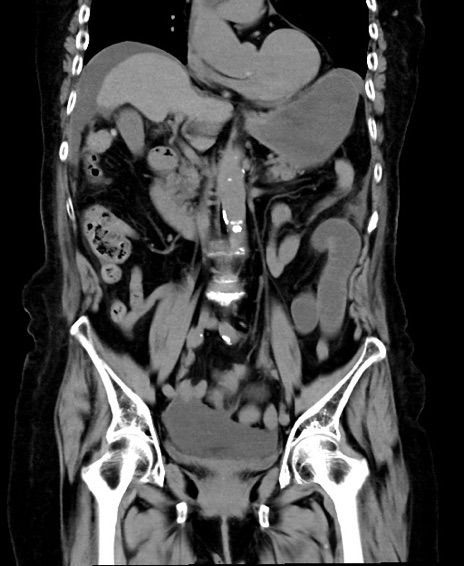

横断像